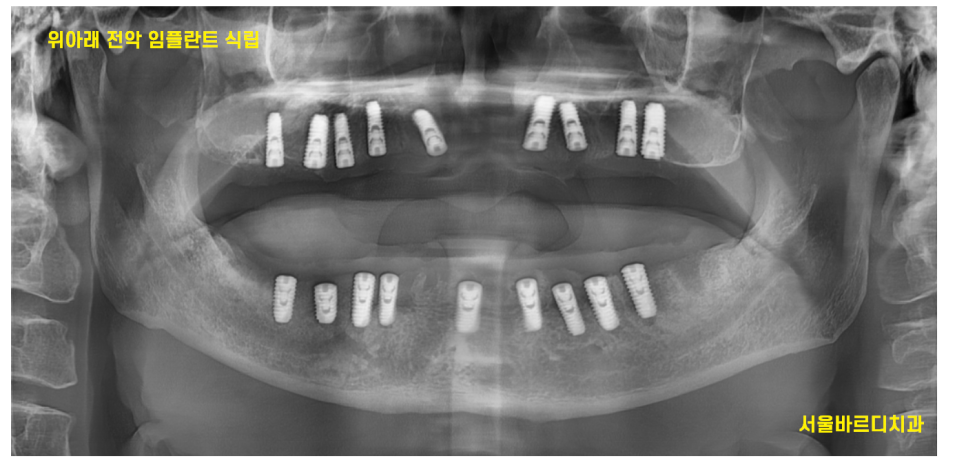

고덕역 치과 틀니쓰다 위아래 전악 임플란트 재건했습니다.

당일 한번에 위아래 전악 임플란트를 식립하기로 하였습니다.

수술 당일 사진입니다 하핳 231109

수술은 하루에 전악이 이루어졌습니다.

231109